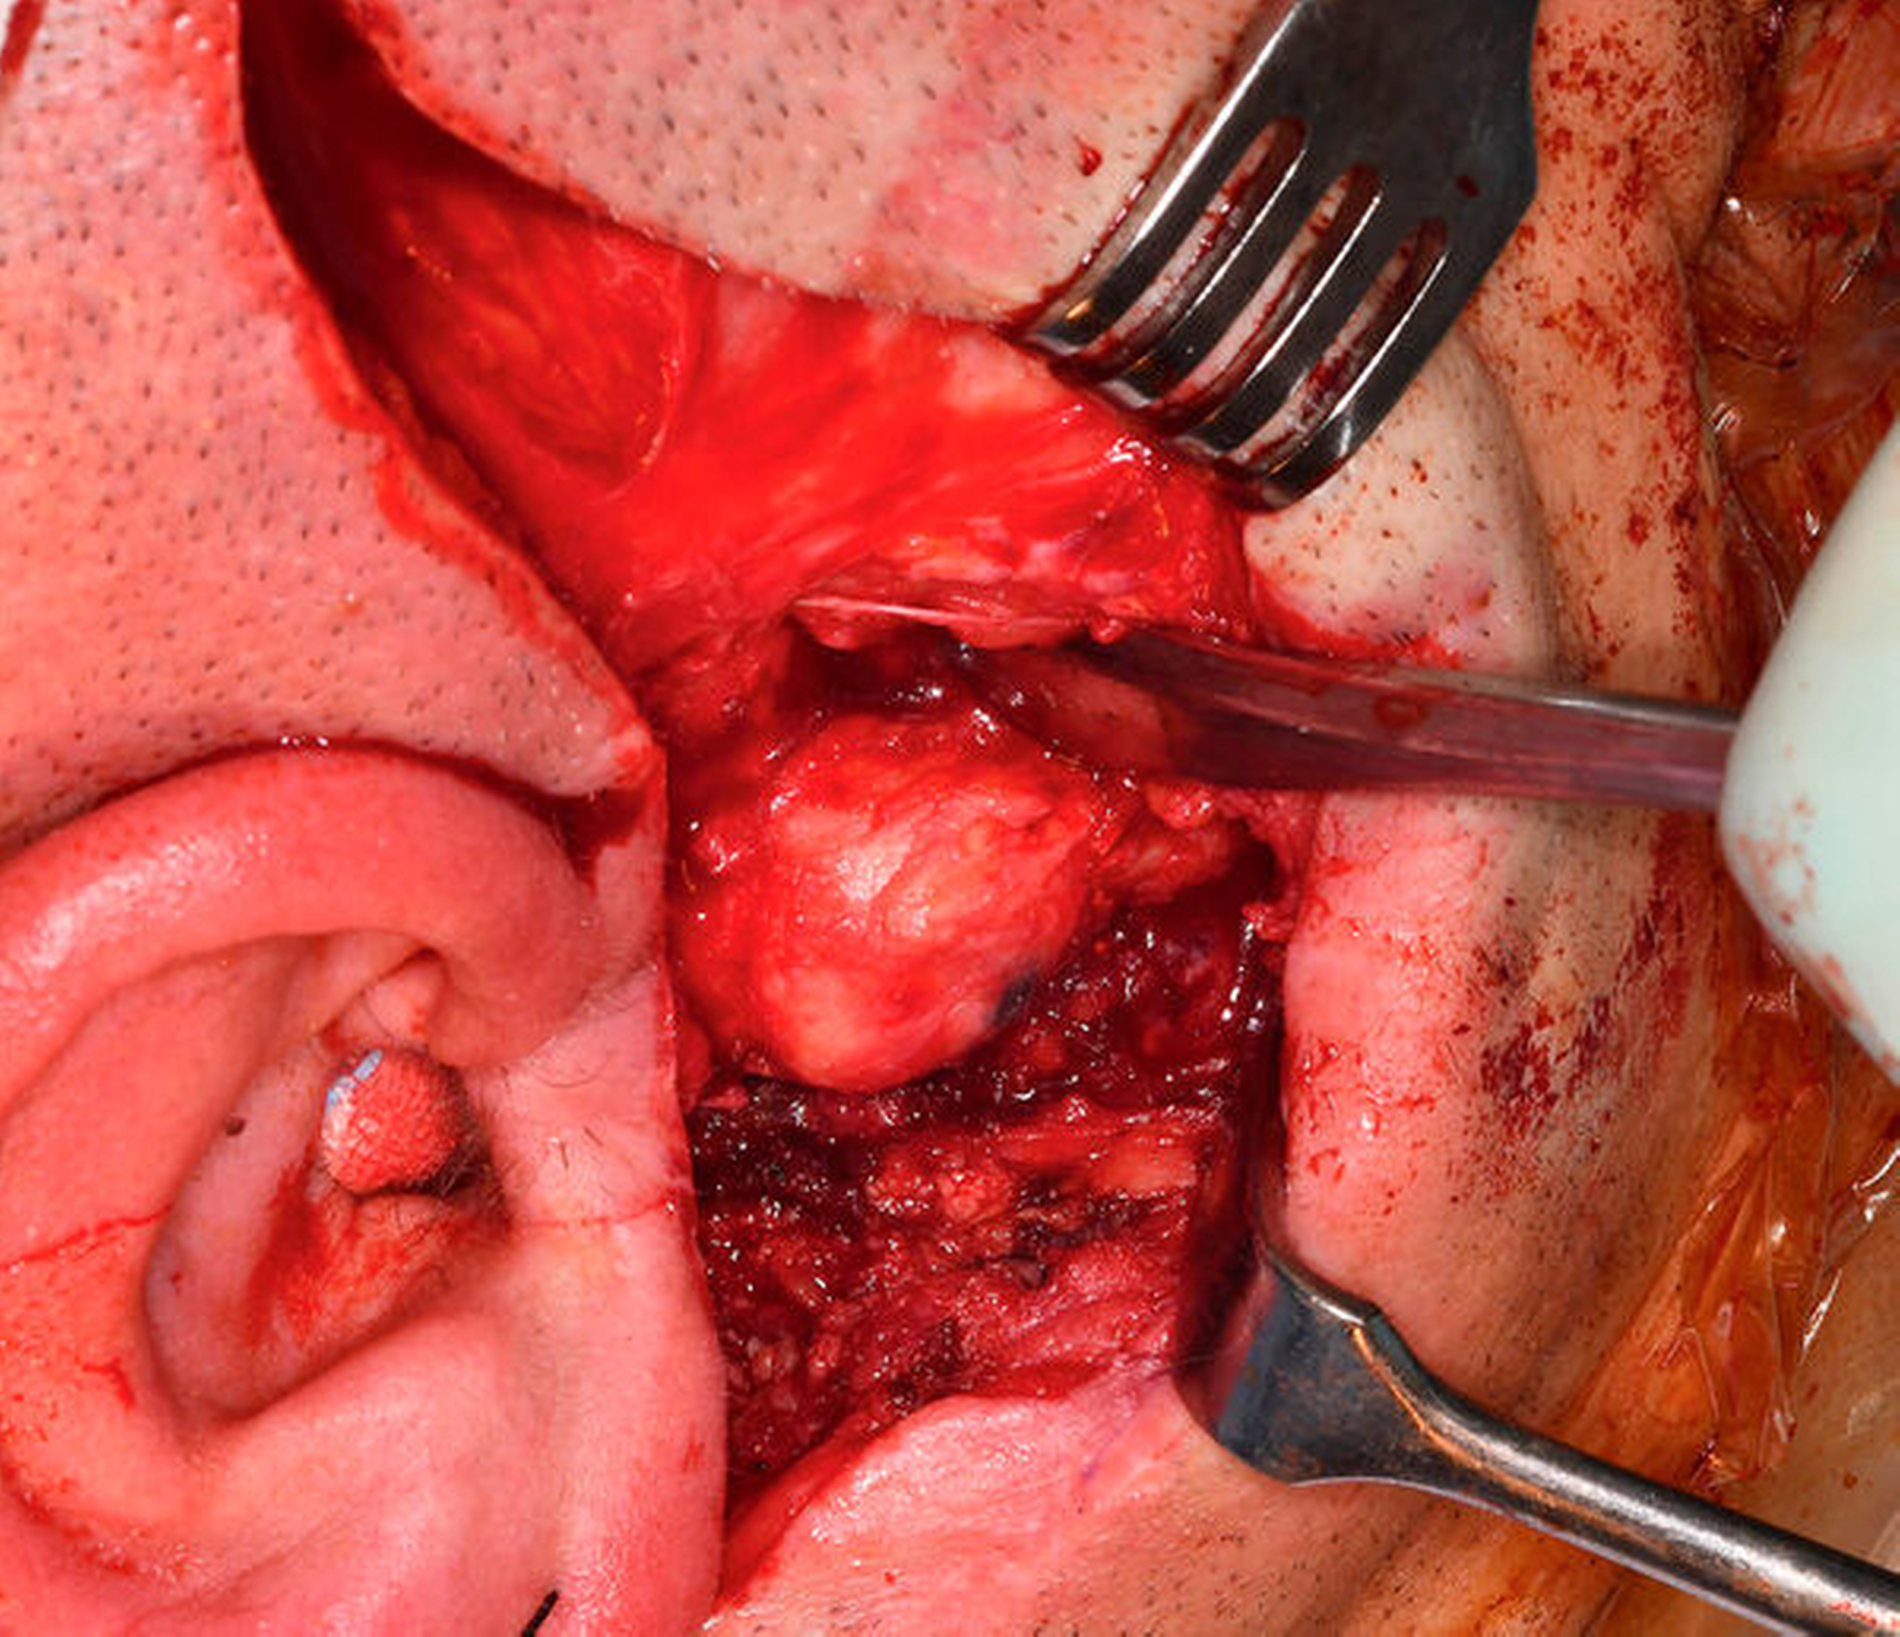

Nach Extraktion der nicht erhaltungswürdigen Zähne 17, 16, 12–27, 36, 46 und 47 und Eingliederung der präformierten Ober- und Unterkiefer-Intermediatprothese folgte die Oberkieferosteotomie in der Le-Fort-I-Ebene mit Neuausrichtung und Osteosynthese unter Verwendung eines CAD/CAM-gefertigten Okklusions-Zwischensplints. Ein zeitgleich gehobener und als Interpositionsosteoplastik eingebrachter kortikospongiöser Knochenspan vom Beckenkamm diente zur Vergrößerung der knöchernen Anlagerungsfläche nach Oberkiefervorverlagerung (Abbildung 4). Die anschließende Darstellung des rechten Kiefergelenks erfolgte über die Extension des präaurikulären Zugangs entlang der vorbestehenden Narbe nach retromandibulär, die Darstellung des linken Kiefergelenks über einen nach parietal extendierten präaurikulären und zusätzlich retromandibulären Zugang.

Danach erfolgte die beidseitige Abtragung der Ankylosemasse und die Resektion der deformierten Kiefergelenke mit modellierender Glättung der Jochbogenunterseite zur Schaffung einer Anlagefläche für die anschließend eingebrachten Fossakomponenten (Zimmer Biomet Holdings, Warsaw, Indiana, USA) (Abbildung 5). Nach Eingliederung der Unterkiefer-Intermediatprothese sowie des Zielokklusionssplints konnten die patientenspezifischen Kiefergelenk-Endoprothesen (Zimmer Biomet Holdings, Warsaw, Indiana, USA) (Abbildung 6) problemlos eingebracht und mit Osteosyntheseschrauben am ortsständigen Unterkiefer fixiert werden.